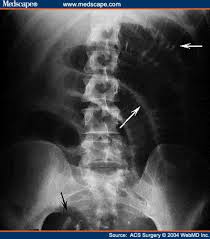

valvulae conniventes